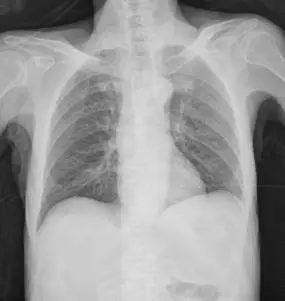

一主訴腹部急性劇痛而且身體虛弱的病人求診。仰臥胸部 X 光檢查和側臥腹部 X 光檢查( cross-table, decubitus view)呈現如二附圖。下列那一項初診斷最正確? 圖片描述 圖片描述

急性腹痛合併身體虛弱的臨床型態,影像學上最重要的判讀要點是偵測自由空氣(pneumoperitoneum),進一步推測最可能的穿孔部位。supine chest X-ray 與 cross-table lateral decubitus 片是早期篩檢自由腹腔氣體的常用投照方式。

第一張為仰臥胸部 X-ray,肝臟投影(右下肺野下方)可見非肺部之弧形透亮帶,且下方無正常肝組織所需的軟組織密度,呈現“cupola sign”──自由氣體在 supine 狀態下往中央肌腱下累積,彌漫於下胸椎前方之透亮區,界限上方清晰,下緣不規則 (en.wikipedia.org)。